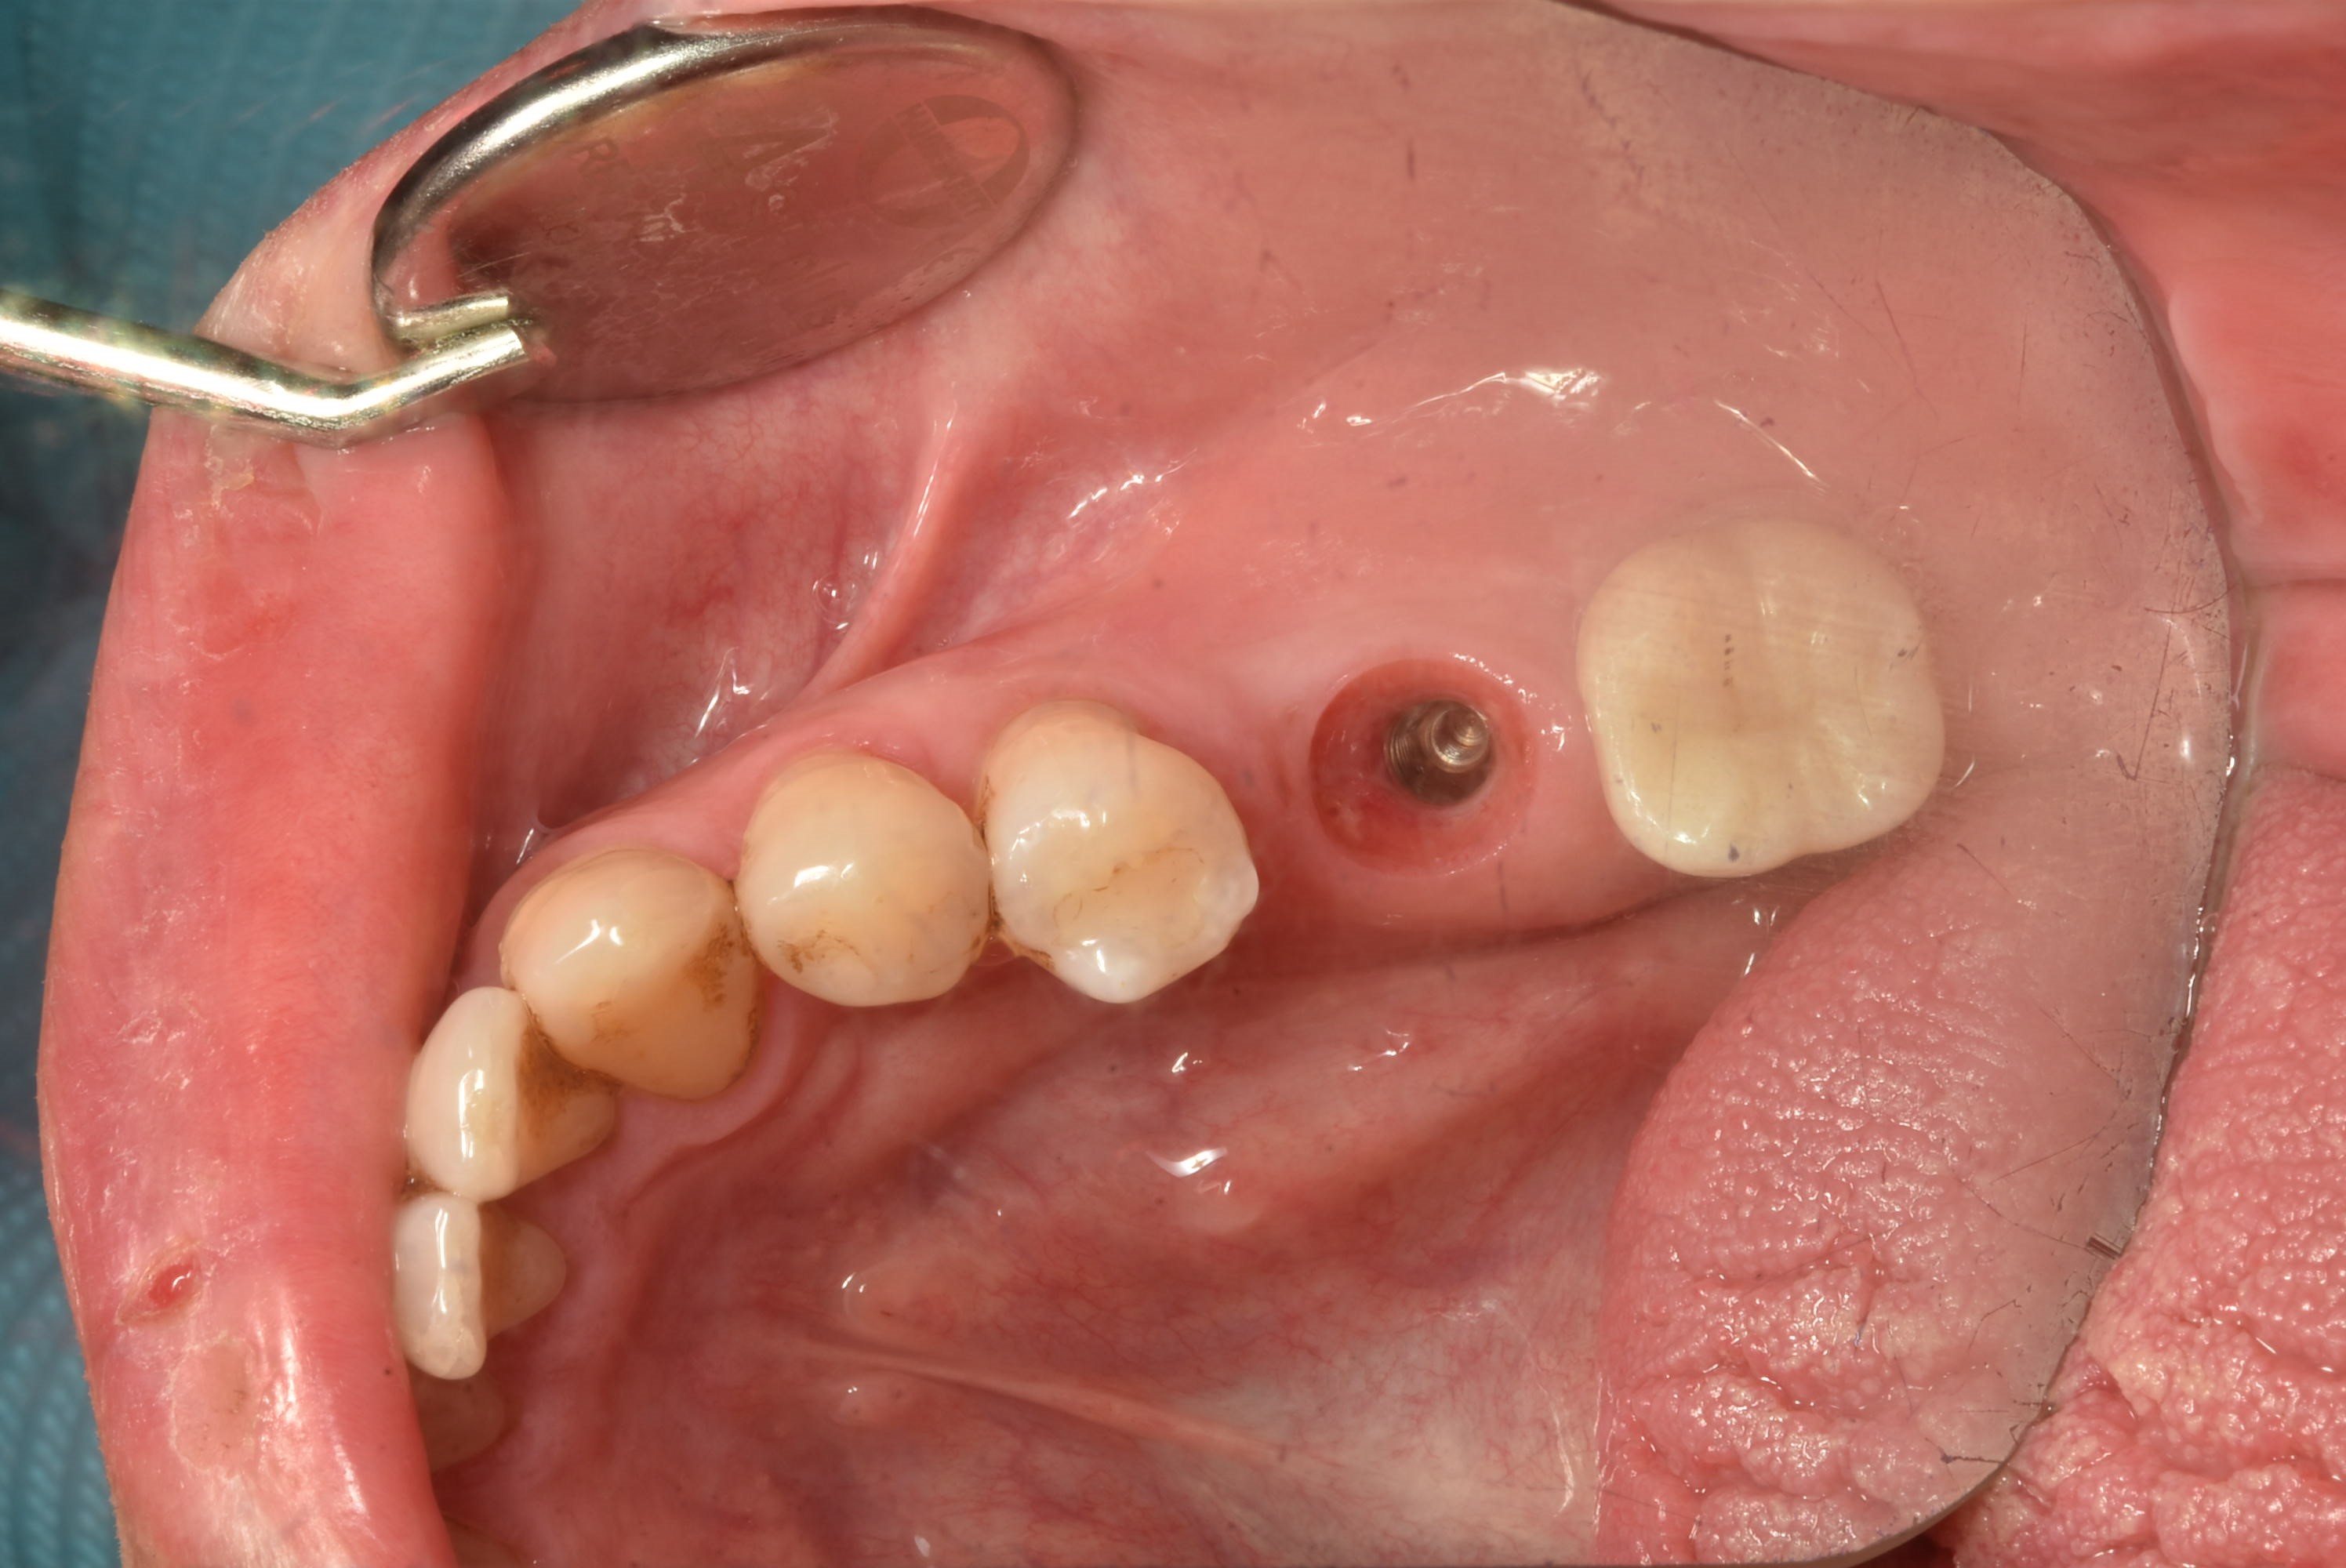

案例四

使用數年的假牙,牙根萎縮,建議拔除及植牙

醫生透過電腦斷層評估骨頭狀況決定植入的植體所放的寬度與深度

植入植體,並鎖上癒合螺帽

2-3個月癒合,7-10天完成假牙 ,試戴、調整咬合高度並鎖上,封填,完成